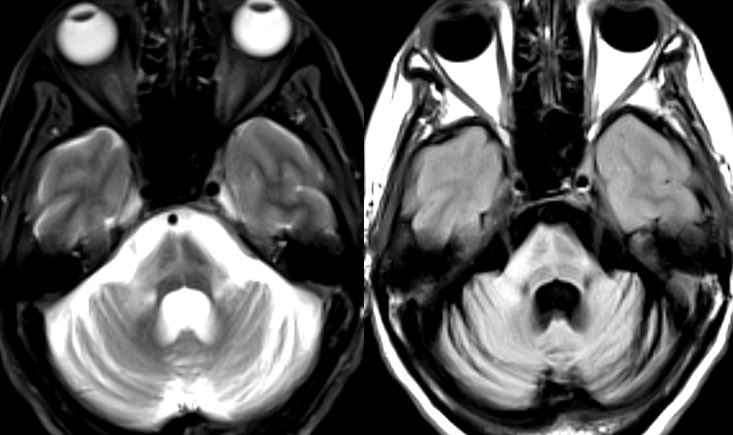

What is the most likely diagnosis in this 55 y/o F presenting w/ 2 years of progressive gait instability, mild dysarthria, bilateral dysmetria, & mild left bradykinesia? 🧠

Answer: Multiple System Atrophy Cerebellar Type (MSA-C)

💡 Hot cross bun sign is specific but NOT pathognomonic (seen in MSA, Spinocerebellar ataxia & others)